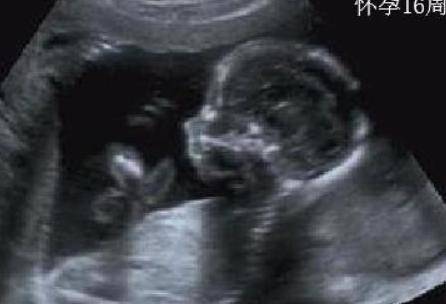

怀孕4个月鉴别男女技巧有哪些?怀孕4个月已经可以看出胎儿性别了,但是以为不能非医学鉴定,很多人就想起民间经验鉴别法。不知道怀孕4个月鉴别男女技巧有什么呢?...

怀孕第4个月,也就是怀孕13-16周的阶段。这时孕妈 度过了胎儿发育最敏感的时期,开始进入稳定期,身体状态和心情也开始逐渐变好...